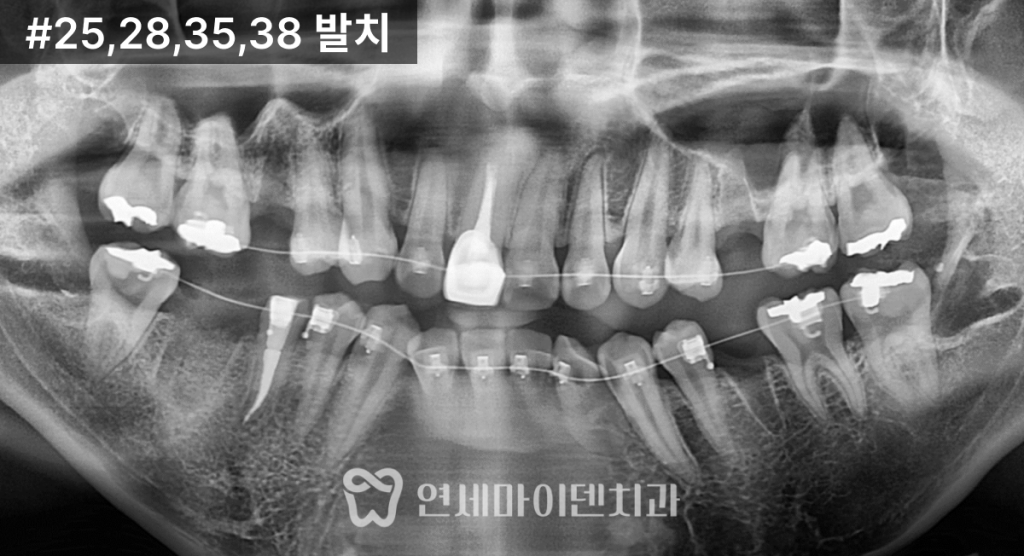

발치 교정 치료 계획

발치 기준은 다음과 같았습니다.

- 신경치료가 불완전하고 예후가 좋지 않은 치아

- 뼈 흡수와 염증 소견이 동반된 치아

이에 따라 오른쪽 아래는 큰어금니(6번),

오른쪽 위와 왼쪽 아래는 5번 치아,

그리고 교합의 대칭을 맞추기 위해

왼쪽 위 역시 5번 치아를 발치했습니다.

문제가 있는 치아를 먼저 정리하면서

동시에 돌출 개선까지 도모한

치료 계획이었습니다.

돌출입 교정 치료 과정

초기 단계 (약 1년 1개월)

발치 공간이 점차 줄어들기 시작했고,

돌출 개선을 위해 미니스크류를 이용해

앞니를 최대한 후방으로 이동시켰습니다.